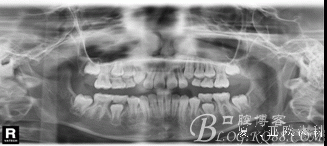

X線頭影測(cè)量值:SNA角77.13 ; SNB角75.73 ; ANB角1.41 ;SND角71.78 ;

U1toA-Pog 2.42 ;IMPA角96.48 ; FH-MP角26.37。

全頜曲面斷層片:尚未萌出的恒牙牙胚均存在。

診 斷:安氏I類錯(cuò)合(III類傾向)。骨骼III類關(guān)系。凹面型:上頜劣生長(zhǎng)、下頜過(guò)生長(zhǎng)。上頜尖牙萌出間隙不足。前牙骨性反咬合。